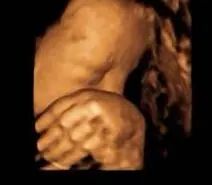

爱妈B已接近孕期的第37周,宝宝几乎已经准备好迎接这个世界。通过最近的B超,我们可以清楚地看到宝宝的面容,非常可爱。宝宝的体重约为6.5磅,身长在19到20英寸之间。他们的肺部和大多数重要器官已经发育成熟,准备在出生后立即发挥功能。尽管在子宫内的空间越来越小,宝宝的活动—如翻身或踢动—依然频繁,有时这些动作会给爱妈带来一些不适。